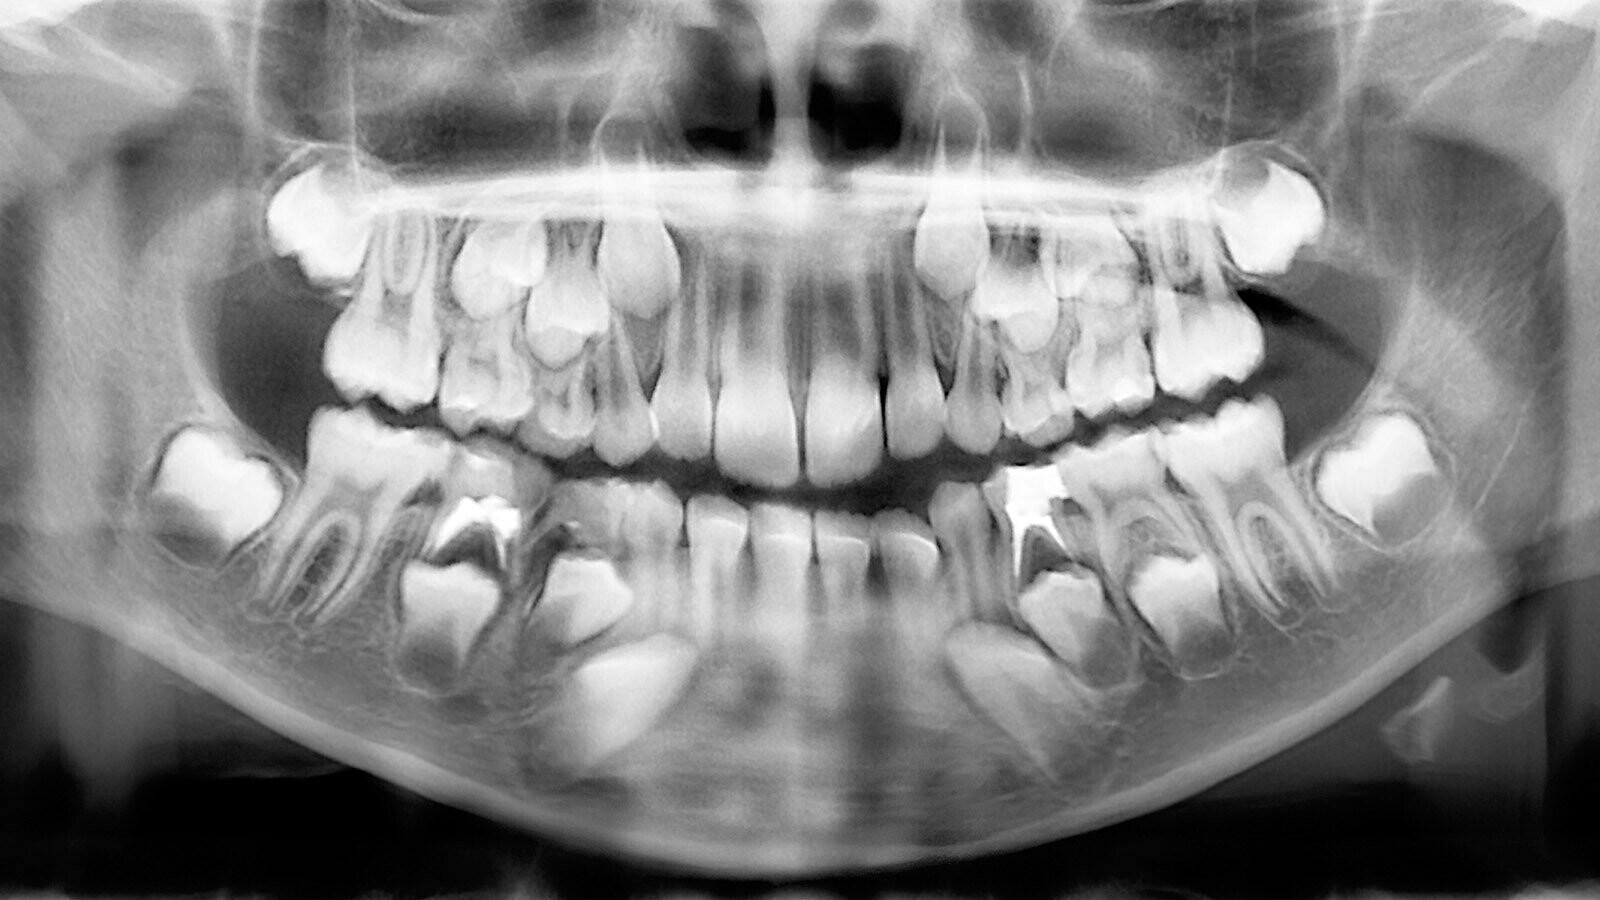

Wisdom Teeth

Extra Teeth